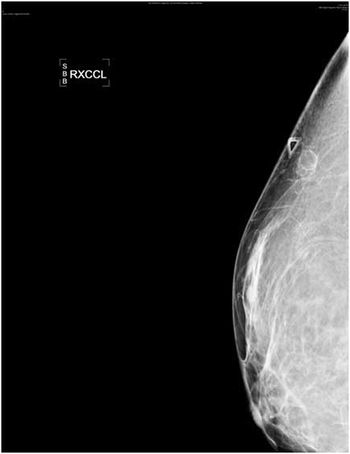

Two Oil Cysts

Clinical History: A female in her early 30s presented to the women’s imaging department. The patient has a history of a bilateral breast lift and breast implants.